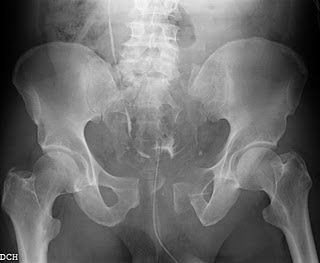

Manejo inicial y clasificacion Fx de Pelvis

TRAUMA ALTA ENERGIA80% PELVIS INESTABLES CURSA CON LESION MUSCULOESQUELETICA SIMULTANEAMORTAIDAD 15-25%FX PELVIS EXPUESTA 2-4%MORTALIAD: 15-80%FX P. EXPUESTA NIÑOS: 12.9%

LIGAMENTOS SACROILIACOS:MAYOR RESISTENCIA CORPORALSINFISIS PUBIS: 15% ESTABILIDAD ANILLO PELVICOMM PISO PELVICO AYUDA A LA ESTABILIDAD DEL APPX FX INESTABLE PELVIS 15-69%: 1-4 PG36-55%: LESION INTRAABDOMINAL6-18%: PELVIC ARTERIAL INJURY